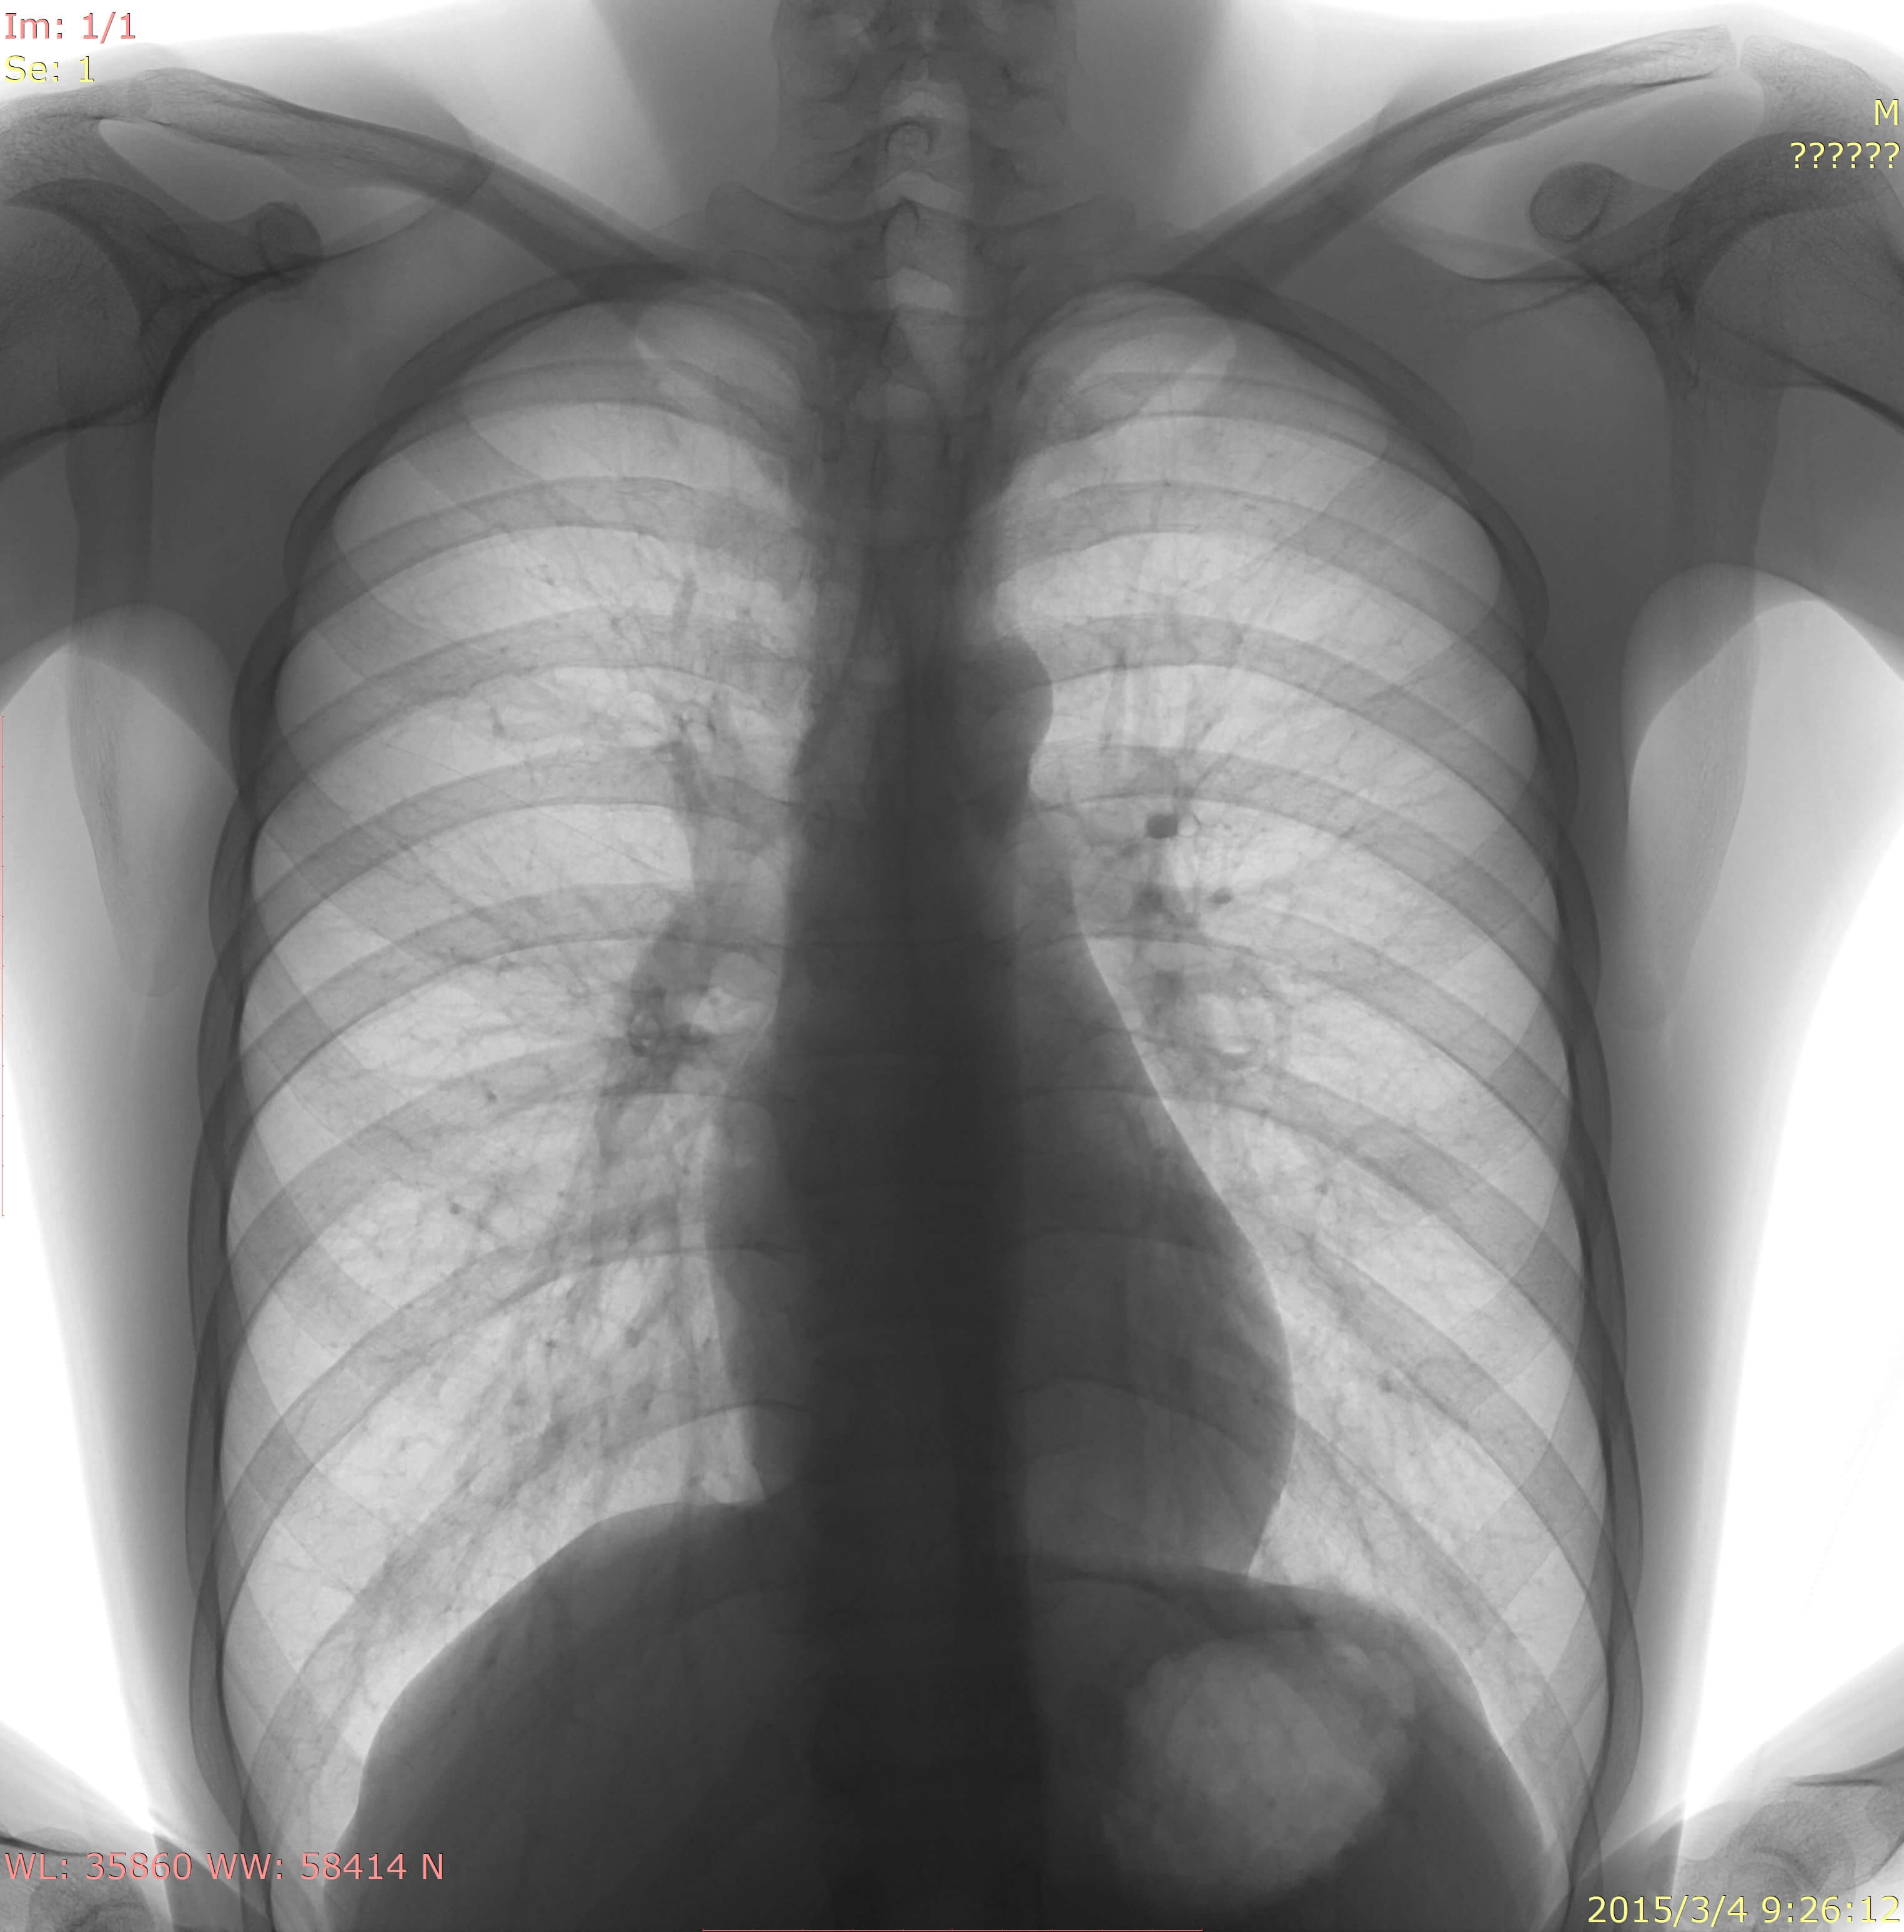

• Clinical Images